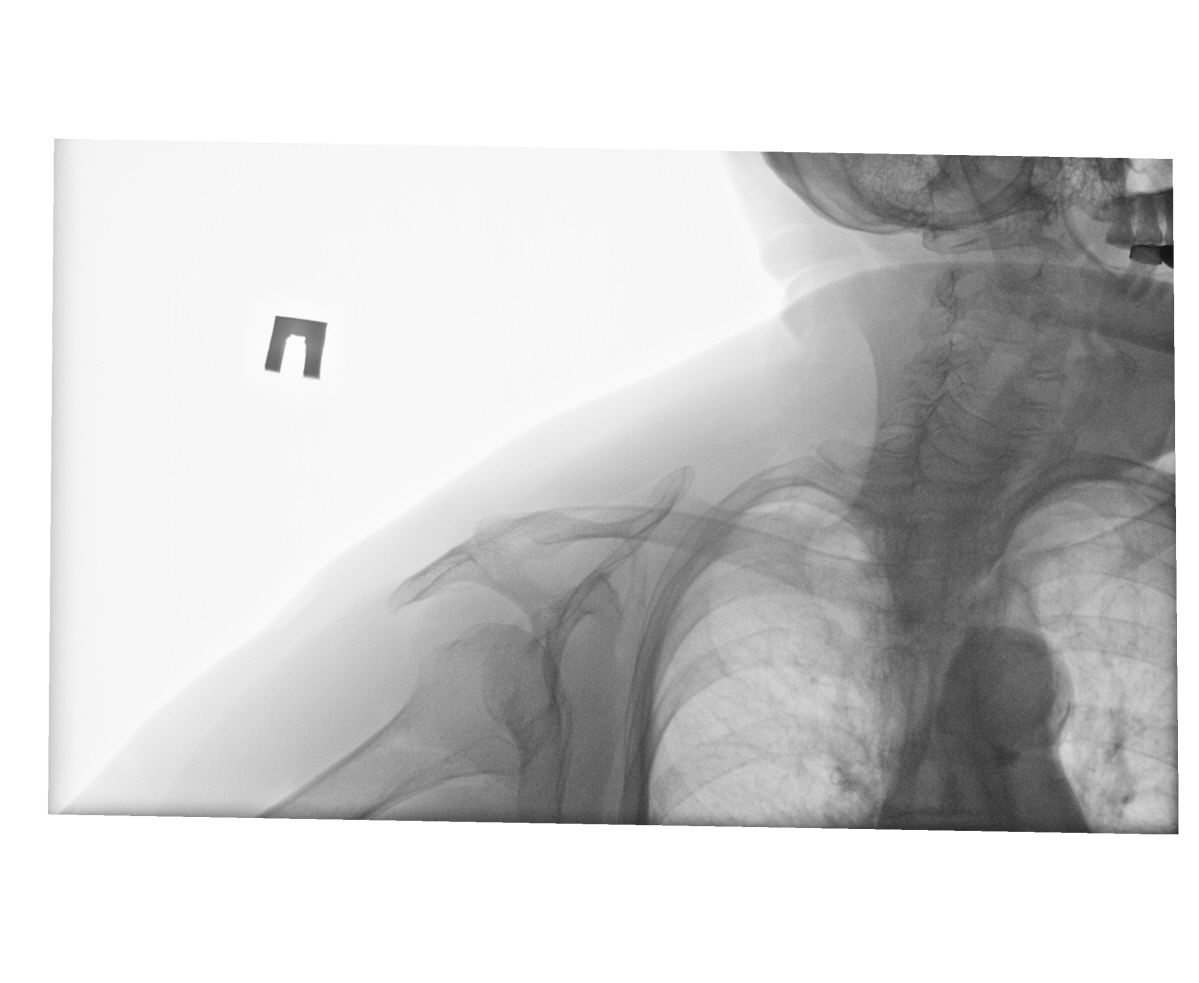

Женщина, 78 лет. в обл.гр/ключичного сочленения видимая опухоль. Образовани е в мягких тканях или все таки из кости? ID:47831 Пнд, 27/01/2014 - 12:52 #1 NIL Не на сайте Был на сайте: 1 неделя 16 часов назад Зарегистрирован: 25.11.2013 - 20:50 Публикации: 18217 Вы не указали, в каком г/ключичном сочленении изменения. Слева, на мой взгляд, костных изменений не определяется. Справа грудинный конец ключицы не визуализируется. "Слушай всех, прислушивайся к немногим, решай сам".© Пнд, 27/01/2014 - 20:14 #2 И.Бондаренко Не на сайте Был на сайте: 1 день 1 час назад Зарегистрирован: 13.09.2011 - 22:55 Публикации: 9213 Туда можно и УЗ датчик поставить. Пнд, 27/01/2014 - 20:27 #3 алкс Не на сайте Был на сайте: 10 лет 5 месяцев назад Зарегистрирован: 24.10.2012 - 22:55 Публикации: 2915 "в обл.гр/ключичного сочленения видимая опухоль." Не видно... Пнд, 27/01/2014 - 22:53 #4 Dima Не на сайте Был на сайте: 7 лет 7 месяцев назад Зарегистрирован: 05.08.2012 - 17:39 Публикации: 2467 По всей видимости артроз грудиноключичного сочленения, УЗИ и МРТ в помощь. Терпимость - это когда прощают чужие ошибки; такт - когда не замечают их. (Артур Шницлер) Втр, 28/01/2014 - 13:37 #5 Mila85 Не на сайте Был на сайте: 3 года 6 месяцев назад Зарегистрирован: 15.03.2012 - 16:59 Публикации: 1790 Ах сколько таких направлений бывает, опухоль в грудинно-ключичном сочленнении, еще и по cito)) Оказывается банальный артроз

Вы не указали, в каком г/ключичном сочленении изменения. Слева, на мой взгляд, костных изменений не определяется. Справа грудинный конец ключицы не визуализируется.

"в обл.гр/ключичного сочленения видимая опухоль." Не видно...

По всей видимости артроз грудиноключичного сочленения, УЗИ и МРТ в помощь.